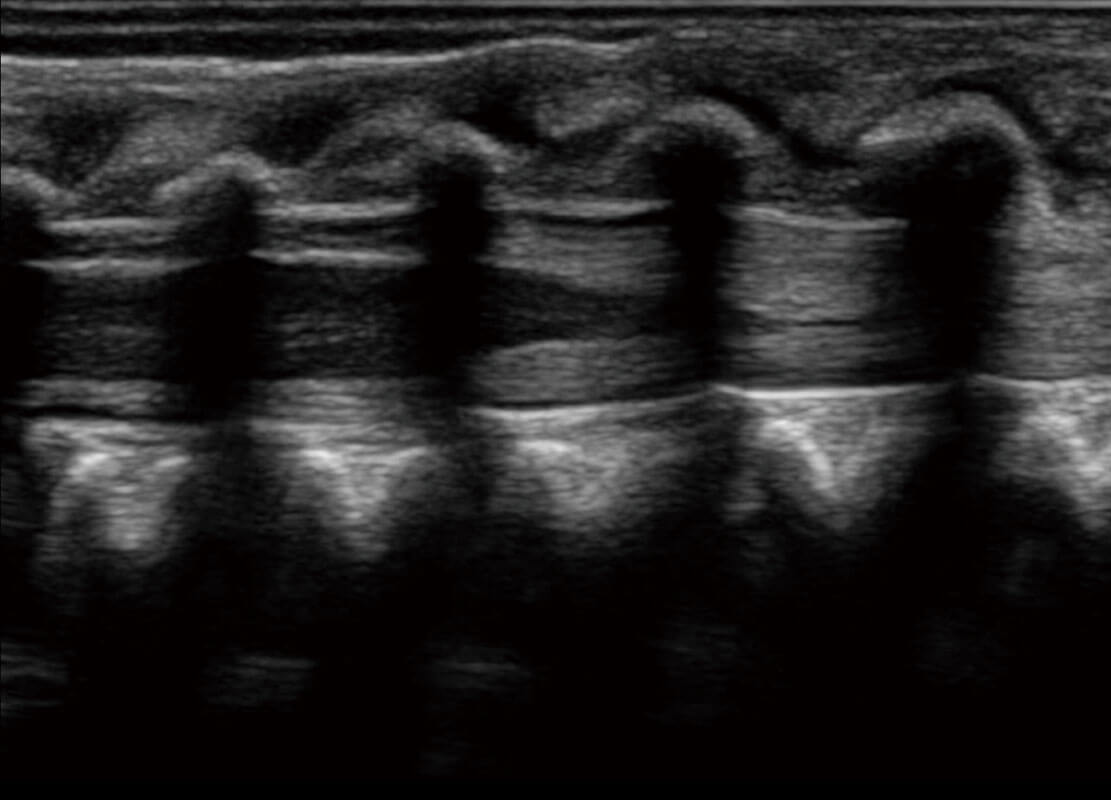

乳腺超声 / 新生儿

P60搭载宽频带线阵探头、宽景成像、弹性成像技术,为您提供乳腺应用方案。P60支持高频相控阵探头、线阵探头、腹部高频探头、腹部微凸探头等,丰富的探头群搭载敏感的彩色血流成像,适用于新生儿多种脏器检测要求,满足新生儿筛查需求。

• 新生儿脊髓圆锥

• 新生儿心脏